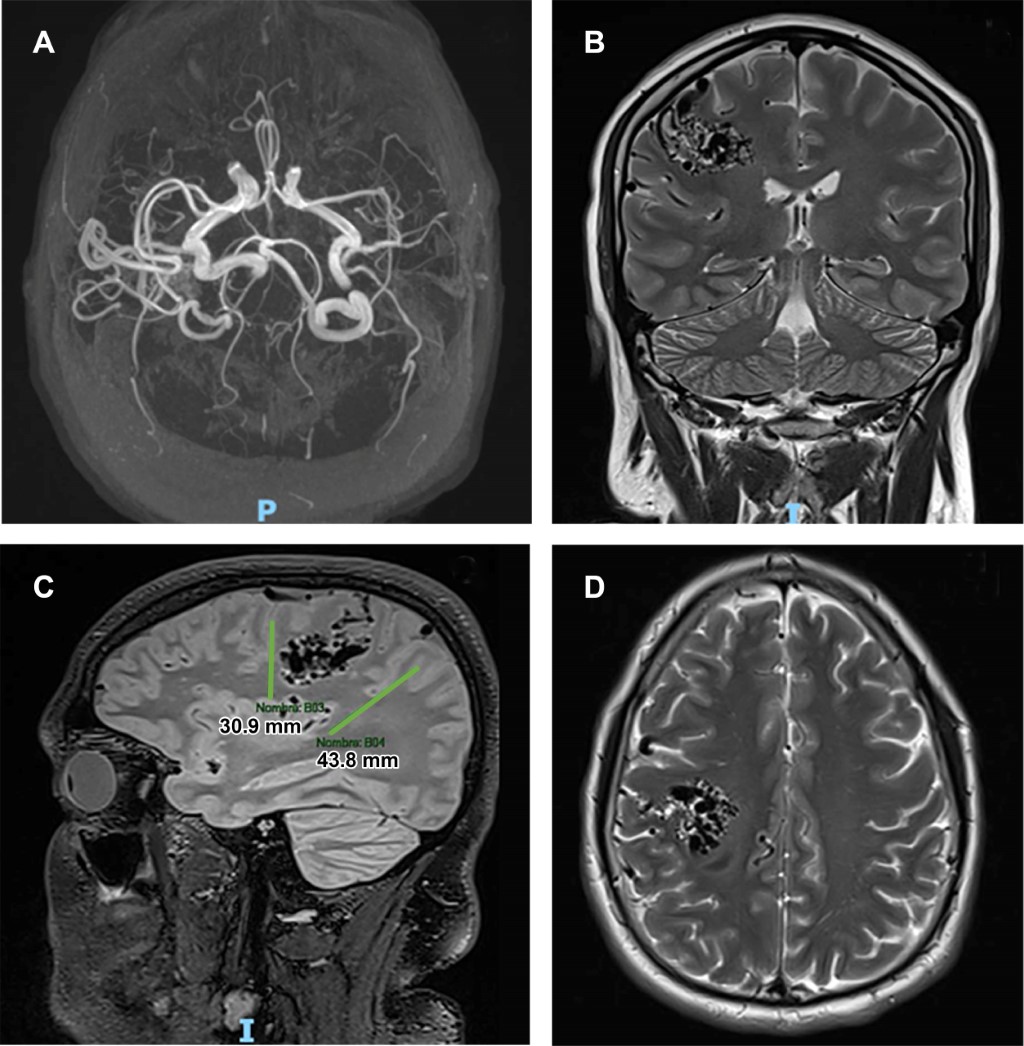

Paciente masculino de 34 años que acudió al Servicio de Urgencias, presentando parestesias, disminución de la fuerza en hemicara izquierda, debilidad en brazo izquierdo, sialorrea y disartria. La exploración neurológica reveló desviación de la comisura labial hacia la derecha e hiporreflexia en el hemicuerpo izquierdo, obteniendo un puntaje de 3 en la escala NIHSS (un punto por paresia parcial, un punto por desviación del brazo izquierdo y un punto por desviación de la pierna izquierda). El paciente también refirió haber experimentado, un mes antes, movimientos involuntarios en el ojo izquierdo, los cuales remitieron espontáneamente. Ante el déficit neurológico focal, se activó el protocolo Stroke y se realizó una resonancia magnética, (Figura 1) la cual no evidenció isquemia ni hemorragia, pero mostró una malformación vascular en el área precentral frontal derecha, con un ovillo de componentes arteriales y venosos de 43 mm en sentido anteroposterior y 30 mm en sentido transverso, con un volumen aproximado de 21 mL. El cuadro clínico resolvió espontáneamente, y el paciente fue dado de alta con seguimiento en consulta externa.

Figura 1